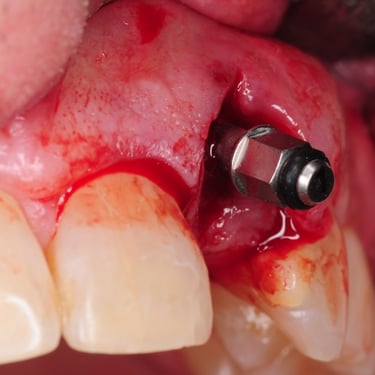

Pérdida de un diente único

La pérdida de un diente único es cuando un solo diente se ha caído o ha sido extraído, y se necesita un implante para reemplazarlo.

Los pacientes pueden notar un espacio donde solía estar el diente. Esta condición puede afectar la estética y la función masticatoria.

El tratamiento incluye la colocación de un implante dental para restaurar el diente perdido.